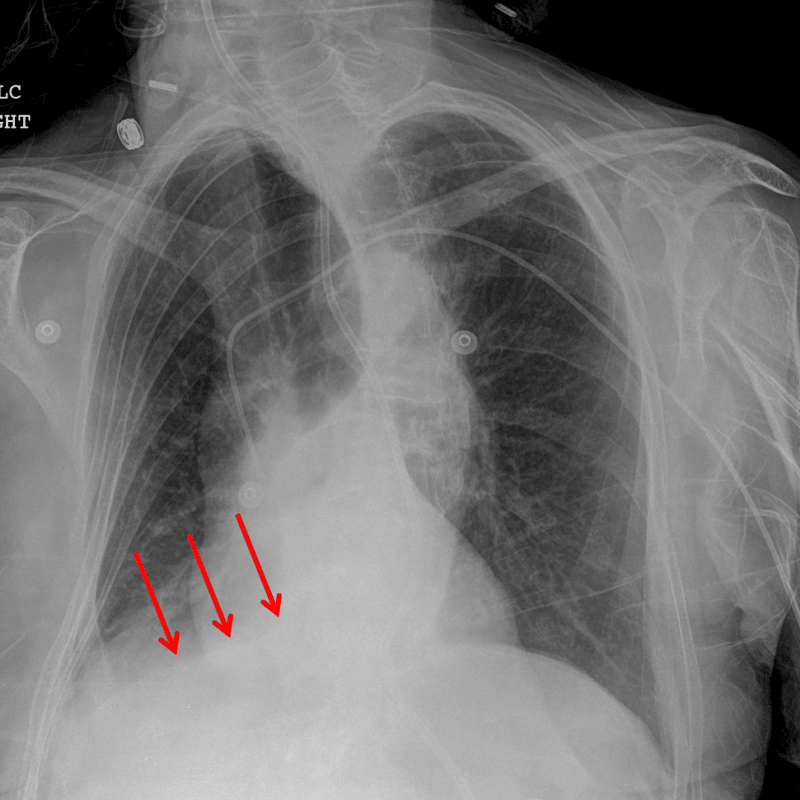

• Triangular opacity at the posteromedial right lung base with loss of the silhouette of the medial and posterior aspect of the right hemidiaphragm

• Evidence of volume loss in the right hemithorax including elevation of the right hemidiaphragm, inferior positioning of the right hilum, rightward mediastinal shift, and crowding of many right ribs

Right lower lobe collapse

• The right lower lobe usually collapses to the inferior/posterior/medial aspect of the right hemithorax, resulting in loss of the medial and posterior silhouette of the right hemidiaphragm. The right heart border silhouette is preserved, which helps distinguish right lower lobe collapse from right middle lobe collapse

Red arrows: right lower lobe collapse.